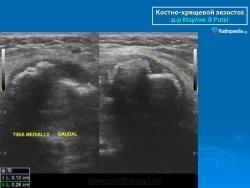

Костно-хрящевые экзостозы (остеохондрома).

Костно-хрящевые экзостозы